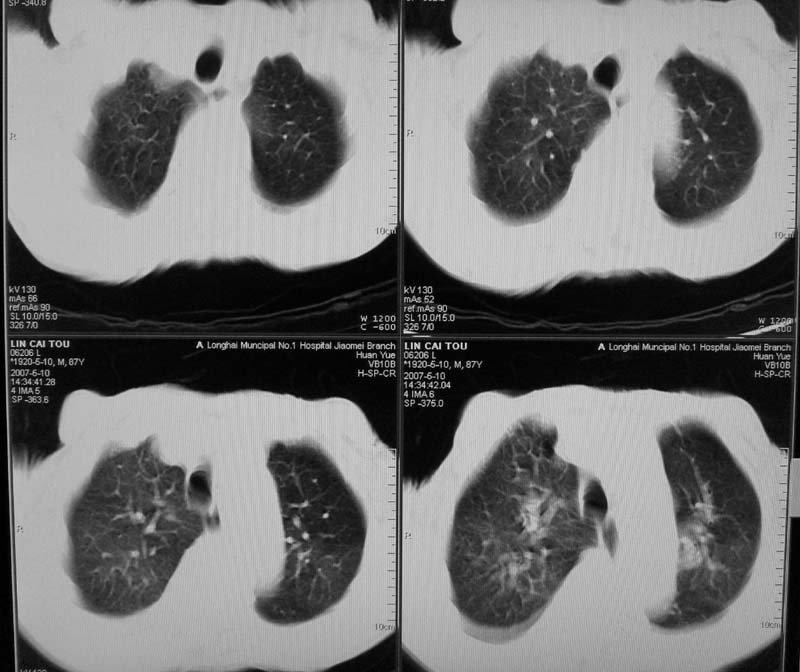

以下是引用小初学者在2007-5-12 16:26:00的发言:[br]1、心衰肺水肿两侧胸腔积液2、心包积液3、心瓣膜钙化